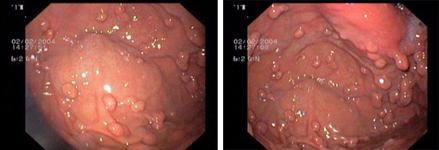

imagen1

Imatge endoscòpica d'un pòlip pla en el còlon, abans (esquerra) i després (dreta) de la resecció